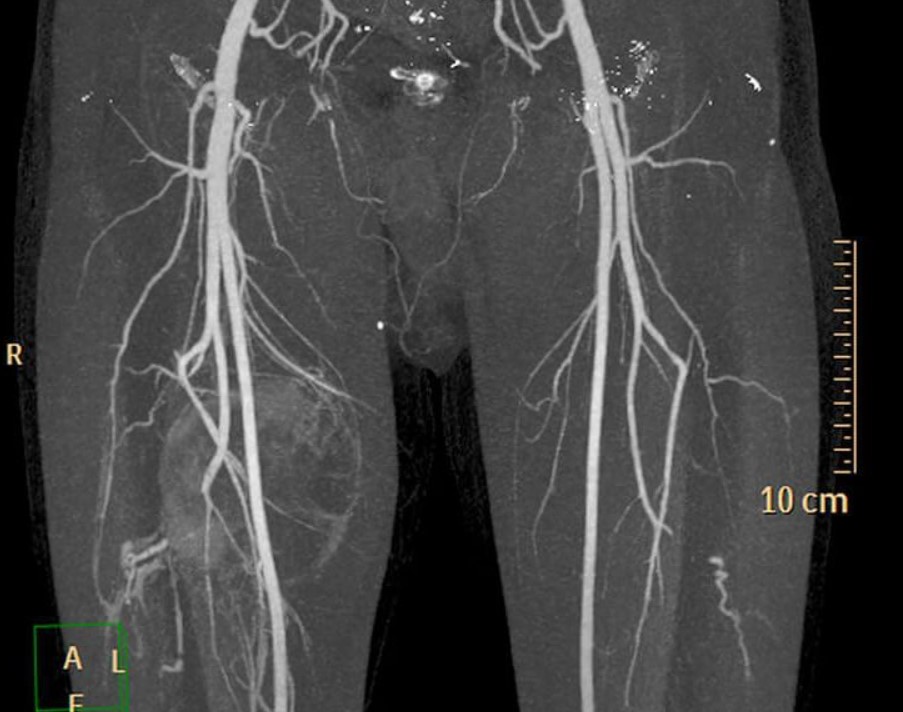

Магнітно-резонансна ангіографія (МР-ангіографія) — це сучасний неінвазивний метод візуалізації судин. На відміну від традиційної ангіографії з катетером, МРТ не потребує проколу артерії, а зображення формуються завдяки впливу магнітного поля, окрім мрт відкритого типу (який не містить таких протоколів).

МР-ангіографія дозволяє побачити не лише структуру, а й функцію вен, а отже, краще обрати тактику лікування — склеротерапію, лазер або комбінований підхід.

Магнітно-резонансна ангіографія (МР-ангіографія) є високоточним методом візуалізації судинної системи, що дозволяє отримати детальні зображення кровоносних судин без використання рентгенівського випромінювання. Цей метод базується на принципах магнітно-резонансної томографії (МРТ) і використовується для оцінки як анатомічних, так і функціональних особливостей кровотоку Клініка DocLife

- Точна оцінка анатомії венозної системи: МР-ангіографія дозволяє детально візуалізувати як поверхневі, так і глибокі вени, виявляючи аномалії, тромбози чи стенози, що можуть впливати на вибір тактики лікування.

МР-ангіографія є цінним інструментом у діагностиці та плануванні лікування варикозного розширення вен. Її використання перед склеротерапією сприяє підвищенню ефективності та безпеки процедури, забезпечуючи індивідуальний підхід до кожного пацієнта та знижуючи ризик ускладнень та рецидивів.